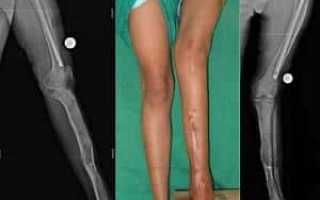

Большая берцовая кость

Фиброзная дисплазия большеберцовой кости приводит к укорочению одной ноги по сравнению с другой, что в свою очередь вызывает нарушения в походке и осанке, хромоту и затруднения в нормальной работе опорно-двигательного аппарата.

Лечение этого состояния осуществляется через хирургическое вмешательство, направленное на пластику пораженных суставов и установку трансплантата.

После операции начинается восстановительный период, в течение которого пациент находится под внимательным наблюдением врачей. В этот период передвижение осуществляется с помощью костылей до полного заживления и восстановления области большеберцовой кости.